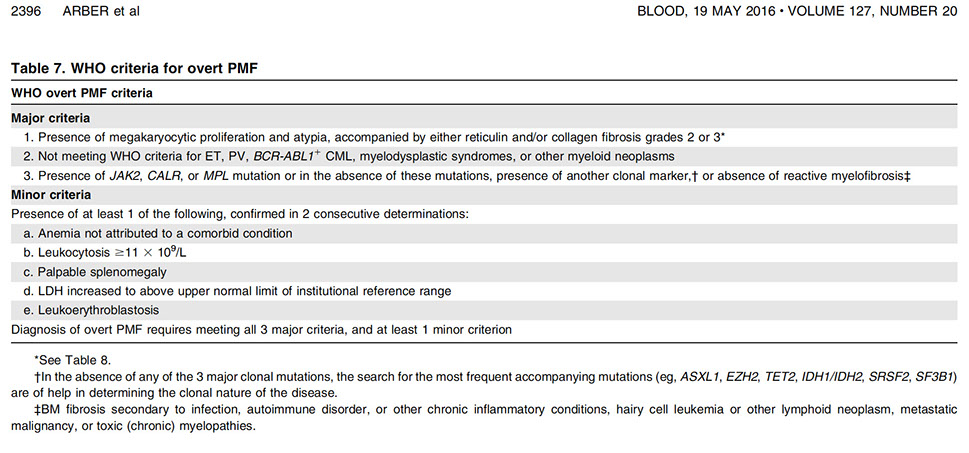

PMF

Primary Myelofibrosis

Primary Myelofibrosis (PMF)

Dx Criteria (need all 3 major and 2 minor):

Major

1.) Mkc prolif + atypia, c fibrosis (if no fibrosis, then need hypercellular BM)

2.) No PV, BCR-ABL1 CML, MDS or other neoplasm

3.) (+) JAK2 V617F or other marker (ie MPL W515K/L)

Minor

1.) Leukoerythroblastosis 2.) Inc serum LDH 3.) Anemia 4.)S-megaly